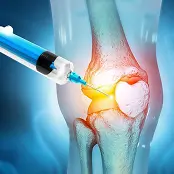

Knee Orthopedic Surgery

The human ankle is a remarkable structure, combining strength and flexibility to support everyday movement. When injury or disease affects its function, the impact on mobility and quality of life can be significant. At Orthopaedics & Rehabilitation Excellence of Miami, patients can access advanced ankle orthopedic surgery and regenerative treatment options designed to restore mobility, reduce pain, and support long-term recovery.